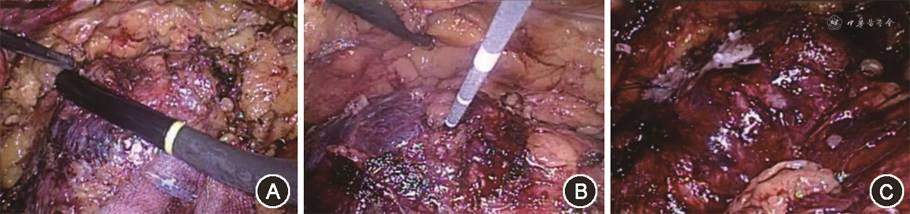

术中应用的微波发生器(南京康友公司,型号KY-2000),由电源、微波发射源、微波消融针、连接电缆、冷却系统组成;微波仪工作频率为2 450 Hz,微波发射源输出功率0~100 W,针型为1.1 cm×18.0 cm,内置水冷却循环系统,防止杆温过高[6, 7]。全身麻醉,经腹腔镜分离肾周脂肪囊,游离肾动脉以备阻断,显露肾肿物,直视或超声定位下将微波消融针穿刺入肿瘤组织内消融。根据肿瘤的大小选择单点或多点穿刺消融,设置50~80 W功率消融3~6 min,可观察到肾肿物在高温下内部水分蒸发,逐渐萎缩,质地变硬,凝固变性呈灰白色,肿瘤周围形成缺血反应带。消融结束,缓慢退出消融针,同时消融穿刺针道,防止肿瘤细胞种植。阻断肾动脉,沿消融后肿瘤环周缺血反应平面切除肿瘤,3-0和2-0倒刺线缝合切面,开放肾动脉,观察创面渗血情况决定是否缝合加固,确保创面无活动性出血(图1)。将标本置入标本袋中取出,送检病理科。